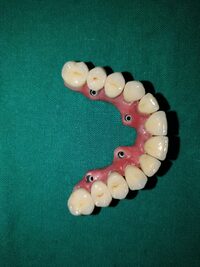

Full Arch Implant

Full arch implants are used to replace an entire upper or lower arch of teeth. Strategically placed implants support a denture-like attachment, offering a natural feel and performance. This solution restores both function and aesthetics.